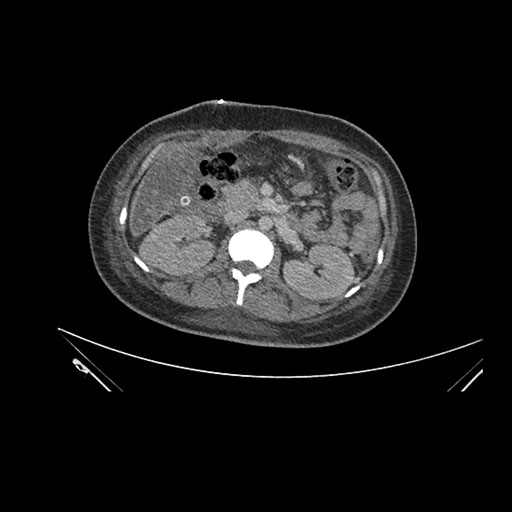

Axial Arterial

Axial Venous

Imaging analysis

Based on initial findings, which issue(s) would you be most concerned about?